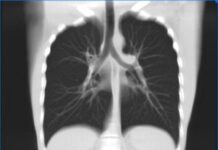

Когда необходимо делать КТ легких?

В настоящее время ни один человек не застрахован от каких-либо критических ситуаций, которые связаны с его здоровьем, именно поэтому необходимо действительно тщательно заботиться о...